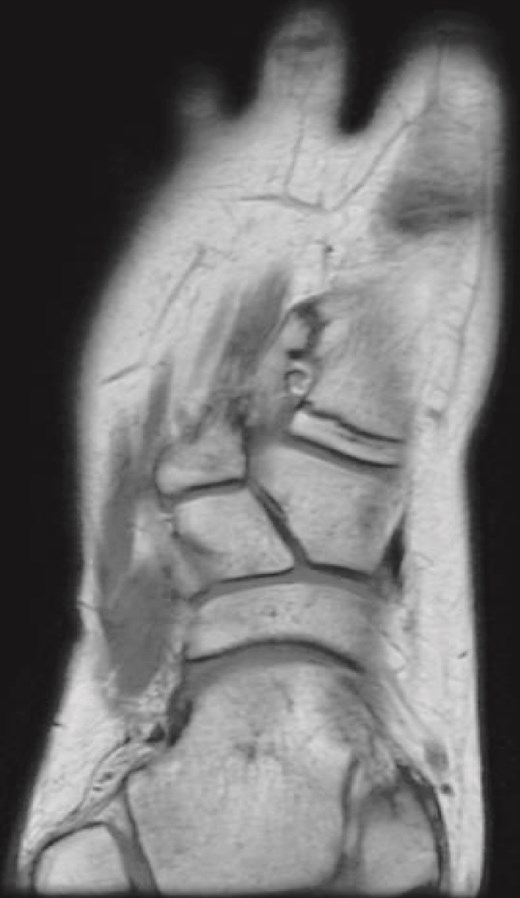

Plain radiographs revealed a bony mass extending from the medial cuneiform to the first metatarsal, with the first and second intermetatarsal space widening (Fig. 1). Magnetic resonance imaging (MRI) was performed to better characterize the mass (Fig. 2). Musculoskeletal radiologists reported the presence of an abnormal rudimentary bone that was interposed between the first and second metatarsal bones, with pseudo-articulation and ankylosis with the lateral aspect of the mid-metatarsal shaft of the hallux, causing widening and deformity, suggesting a supernumerary rudimentary metatarsal bone. An osteochondroma was also considered in the differential diagnosis, but the cartilage cap was not clearly visible. As daily activities were significantly affected, the patient’s guardian preferred surgical excision over more conservative measures, which had previously been unsuccessful.

(a) Lateral radiograph of the right foot demonstrating a bony mass extending from the medial cuneiform to the first metatarsal. (b) Oblique radiograph of the right foot highlighting the abnormal bony outgrowth between the first and second metatarsals. (c) Anteroposterior radiograph showing a bony mass arising from the medial cuneiform extending toward the first metatarsal, with widening of the first intermetatarsal space.